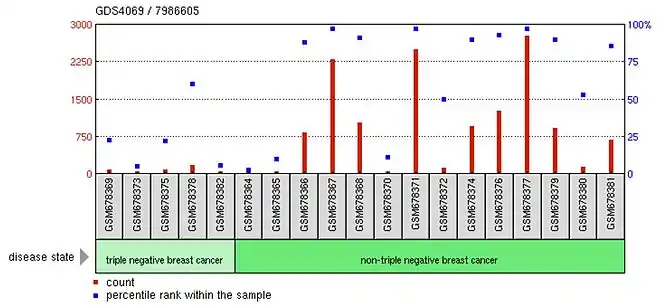

POTEB is expressed at high levels in the human prostate, ovary, and testes. However, there is also evidence to show that it is expressed at low levels in embryonic stem cells, the nasopharyngeal region, and in breast tissue.[12][13] In embryonic stem cells, differentiation is likely to turn off the expression of POTEB while in breast cancer, triple negative cells are found to have no POTEB expression suggesting a role in cancer-activated pathways.[13]

POTEB expression is low or completely reduced in triple-negative breast cancer cells when compared to other types of breast cancer cells.[13] This suggests POTEB’s involvement in intracellular signaling pathways that suppress cancer, or in pathways that regulate the normal growth and division of cells.